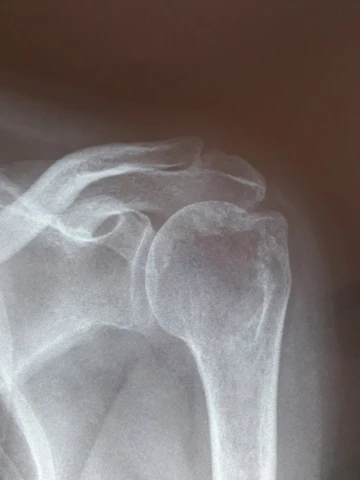

Fracture épaule

img